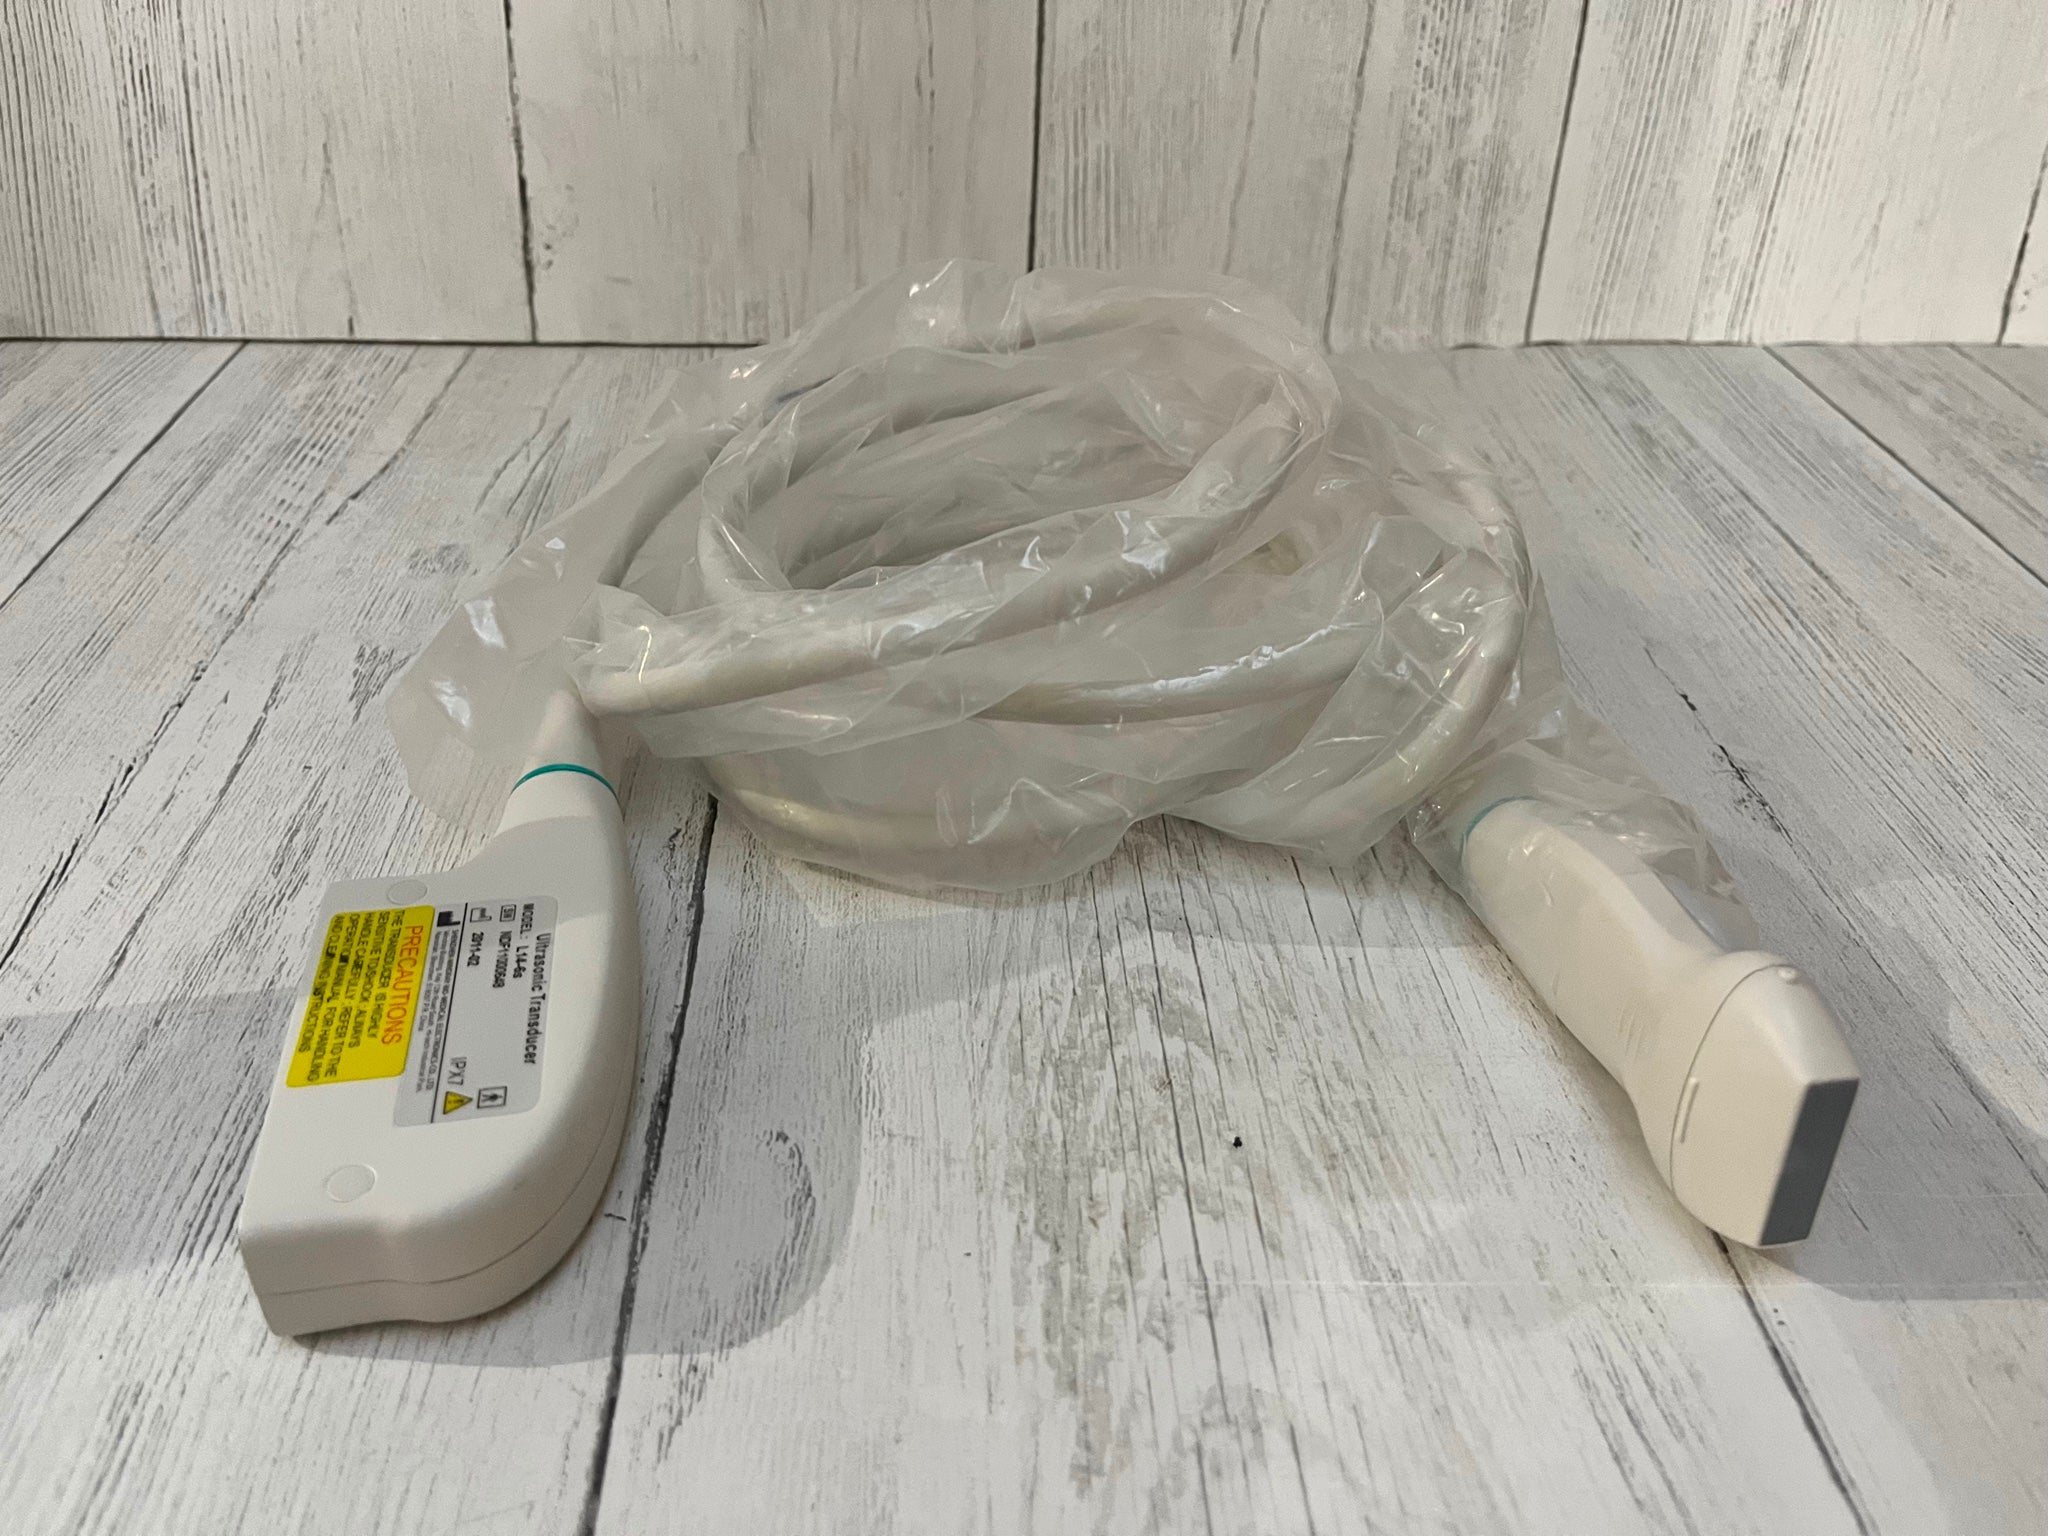

DIAGNOSTIC ULTRASOUND MACHINES FOR SALE

SonoScape S2 with one Trans vaginal Probe Used

Sale price$ 8,198.36